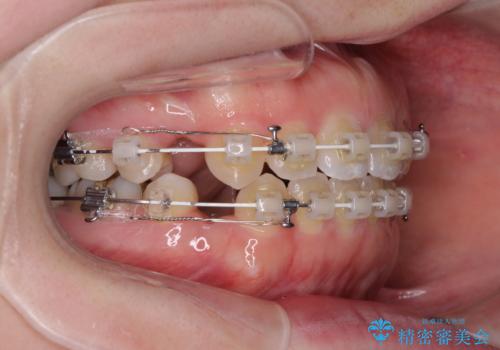

- 矯正装置

- 審美装置

- 口元の膨らみが気になるとのことで来院された患者様です。

非抜歯で口元の突出感を少し改善させる治療も提案しましたが、最大限口元を引っ込めたいとのことでした。

上下左右第一小臼歯4本を抜歯し、ワイヤー装置により矯正治療を行うこととしました。

治療は順調に進み、予定された期間で終了することができました。

装置除去後には、スッキリとした口元となり、大変満足していただきました。